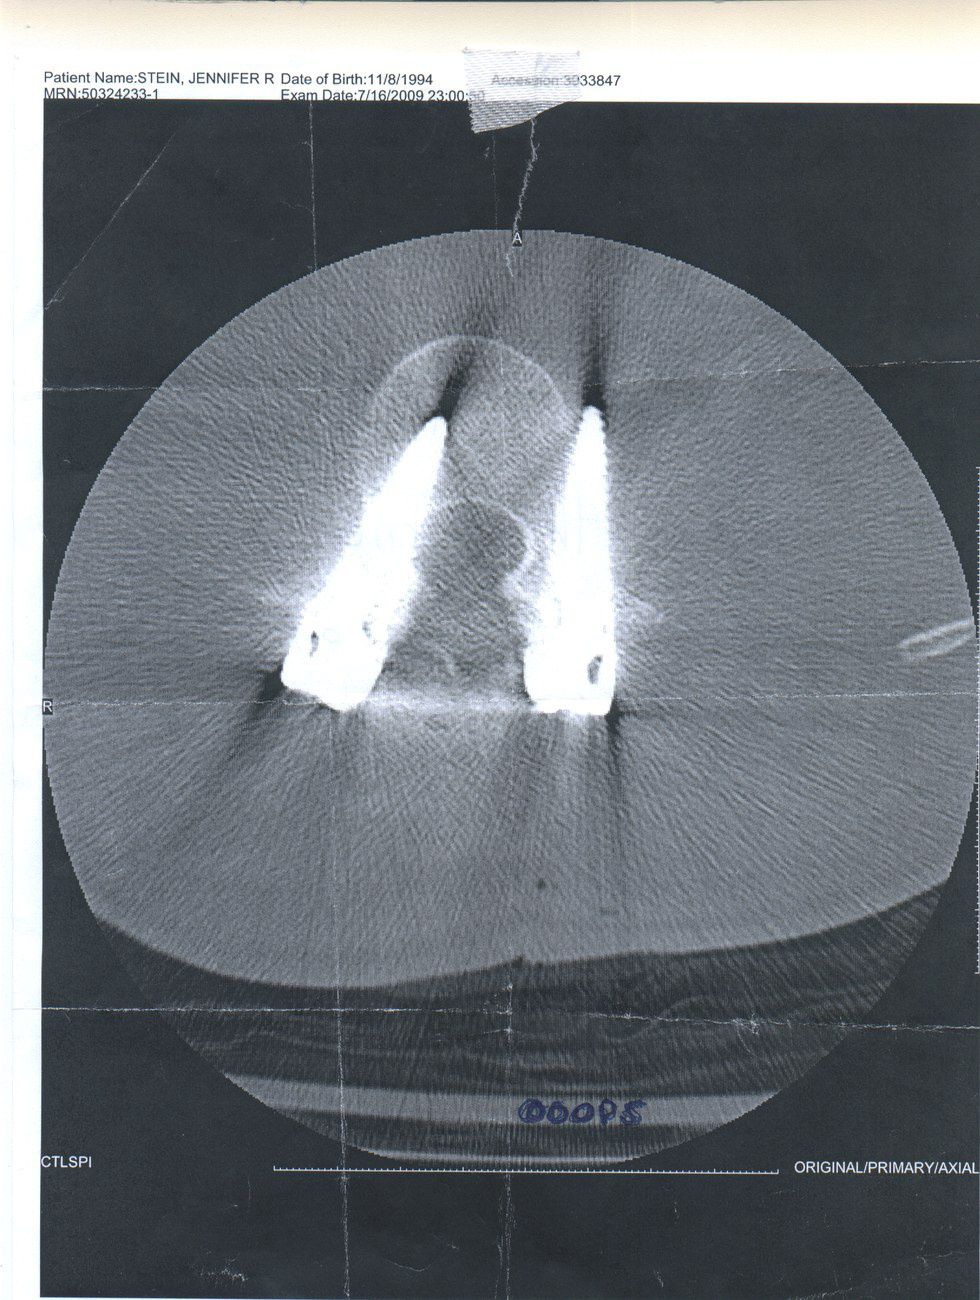

My time in the hospital was interesting. There was a lot of not sleeping that occurred, as I was checked on my a nurse every two hours. They needed to make sure I had enough meds, and to make sure I could still feel all of my limbs. The night the day after my surgery, I was whisked away to have a CAT scan, and the news we got back from the doctors was not good. They had put three of the screws in my lower vertebrae not the correct angle. I needed to have a second surgery. So on the 17th of July, I remember they disconnected me from my morphine drip and knocked me out for a second five hour surgery.

[Note: the "ooops" written in by the doctors]